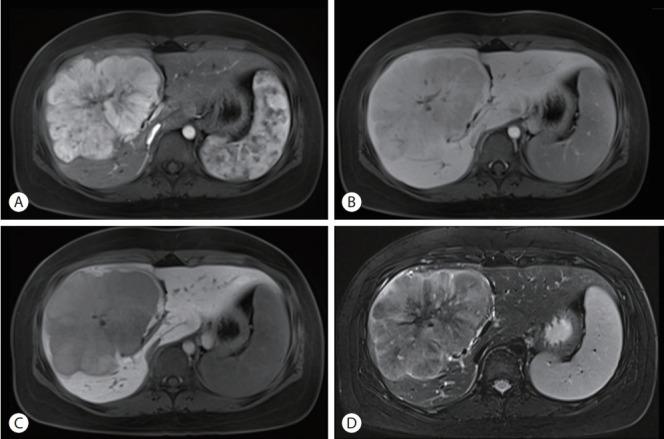

Fibrolamellar hepatocellular carcinoma that was successfully treated with surgical resection: a case report.

Fibrolamellar hepatocellular carcinoma (FLHCC) is a rare malignant hepatic cancer with characteristics that differ from those of typical hepatocellular carcinoma (HCC). Unlike conventional HCC, FLHCC is common in young patients without any underlying liver disease and is known to be associated with a unique gene mutation. This cancer type is rare in Asia, with only a few cases being reported in Korea. We report a case of FLHCC in a young woman that successfully underwent surgical resection. The efficacy of alternative treatments, such as transarterial chemoembolization or systemic chemotherapies, has not yet been established. To conclude, early diagnosis and appropriate surgical resection are important for the treatment of FLHCC.

纤维板层型肝细胞癌(FLHCC)是一种罕见的恶性肝癌,其特征与典型肝细胞癌(HCC)不同。与传统HCC不同,FLHCC在无任何潜在肝脏疾病的年轻患者中较为常见,且已知与一种独特的基因突变有关。这种癌症类型在亚洲很罕见,韩国仅报告了少数病例。我们报告了一例年轻女性FLHCC患者成功接受手术切除的病例。经动脉化疗栓塞或全身化疗等替代治疗的疗效尚未确定。总之,早期诊断和适当的手术切除对FLHCC的治疗很重要。